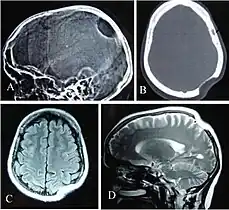

Adult-onset leukoencephalopathy

Because of the importance of the CSF1R gene in myeloid cell survival, maturation, and function, loss-of-function in both inherited copies of the CSF1R gene causes postnatal mortality. Heterozygous mutations in the CSF1R gene prevent downstream CSF1R signaling and cause an autosomal dominant neurodegenerative disease called adult-onset leukoencephalopathy, which is characterized by dementia, executive dysfunction, and seizures. Partial loss of CSF1R in adult-onset leukoencephalopathy causes microglia to exhibit morphological and functional deficits (impaired cytokine production and phagocytosis) which is associated with axonal damage, demyelination, and neuronal loss. Signaling by a DAP12-TREM2 complex in microglia is downstream of CSF1R signaling and is needed for microglia phagocytosis of cellular debris and maintenance of brain homeostasis.[18][12] TREM2 deficiency in cultured myeloid cells prevents stimulation of proliferation by treatment with CSF-1. Similarities between Nasu-Hakola disease (caused by mutations in either DAP12 or TREM2) and adult-onset leukoencephalopathy suggest partial loss of microglia CSF1R signaling promotes neurodegeneration. Defects in neurogenesis and neuronal survival are also seen in adult-onset leukoencephalopathy due to impaired CSF1R signaling in neural progenitor cells.[12]